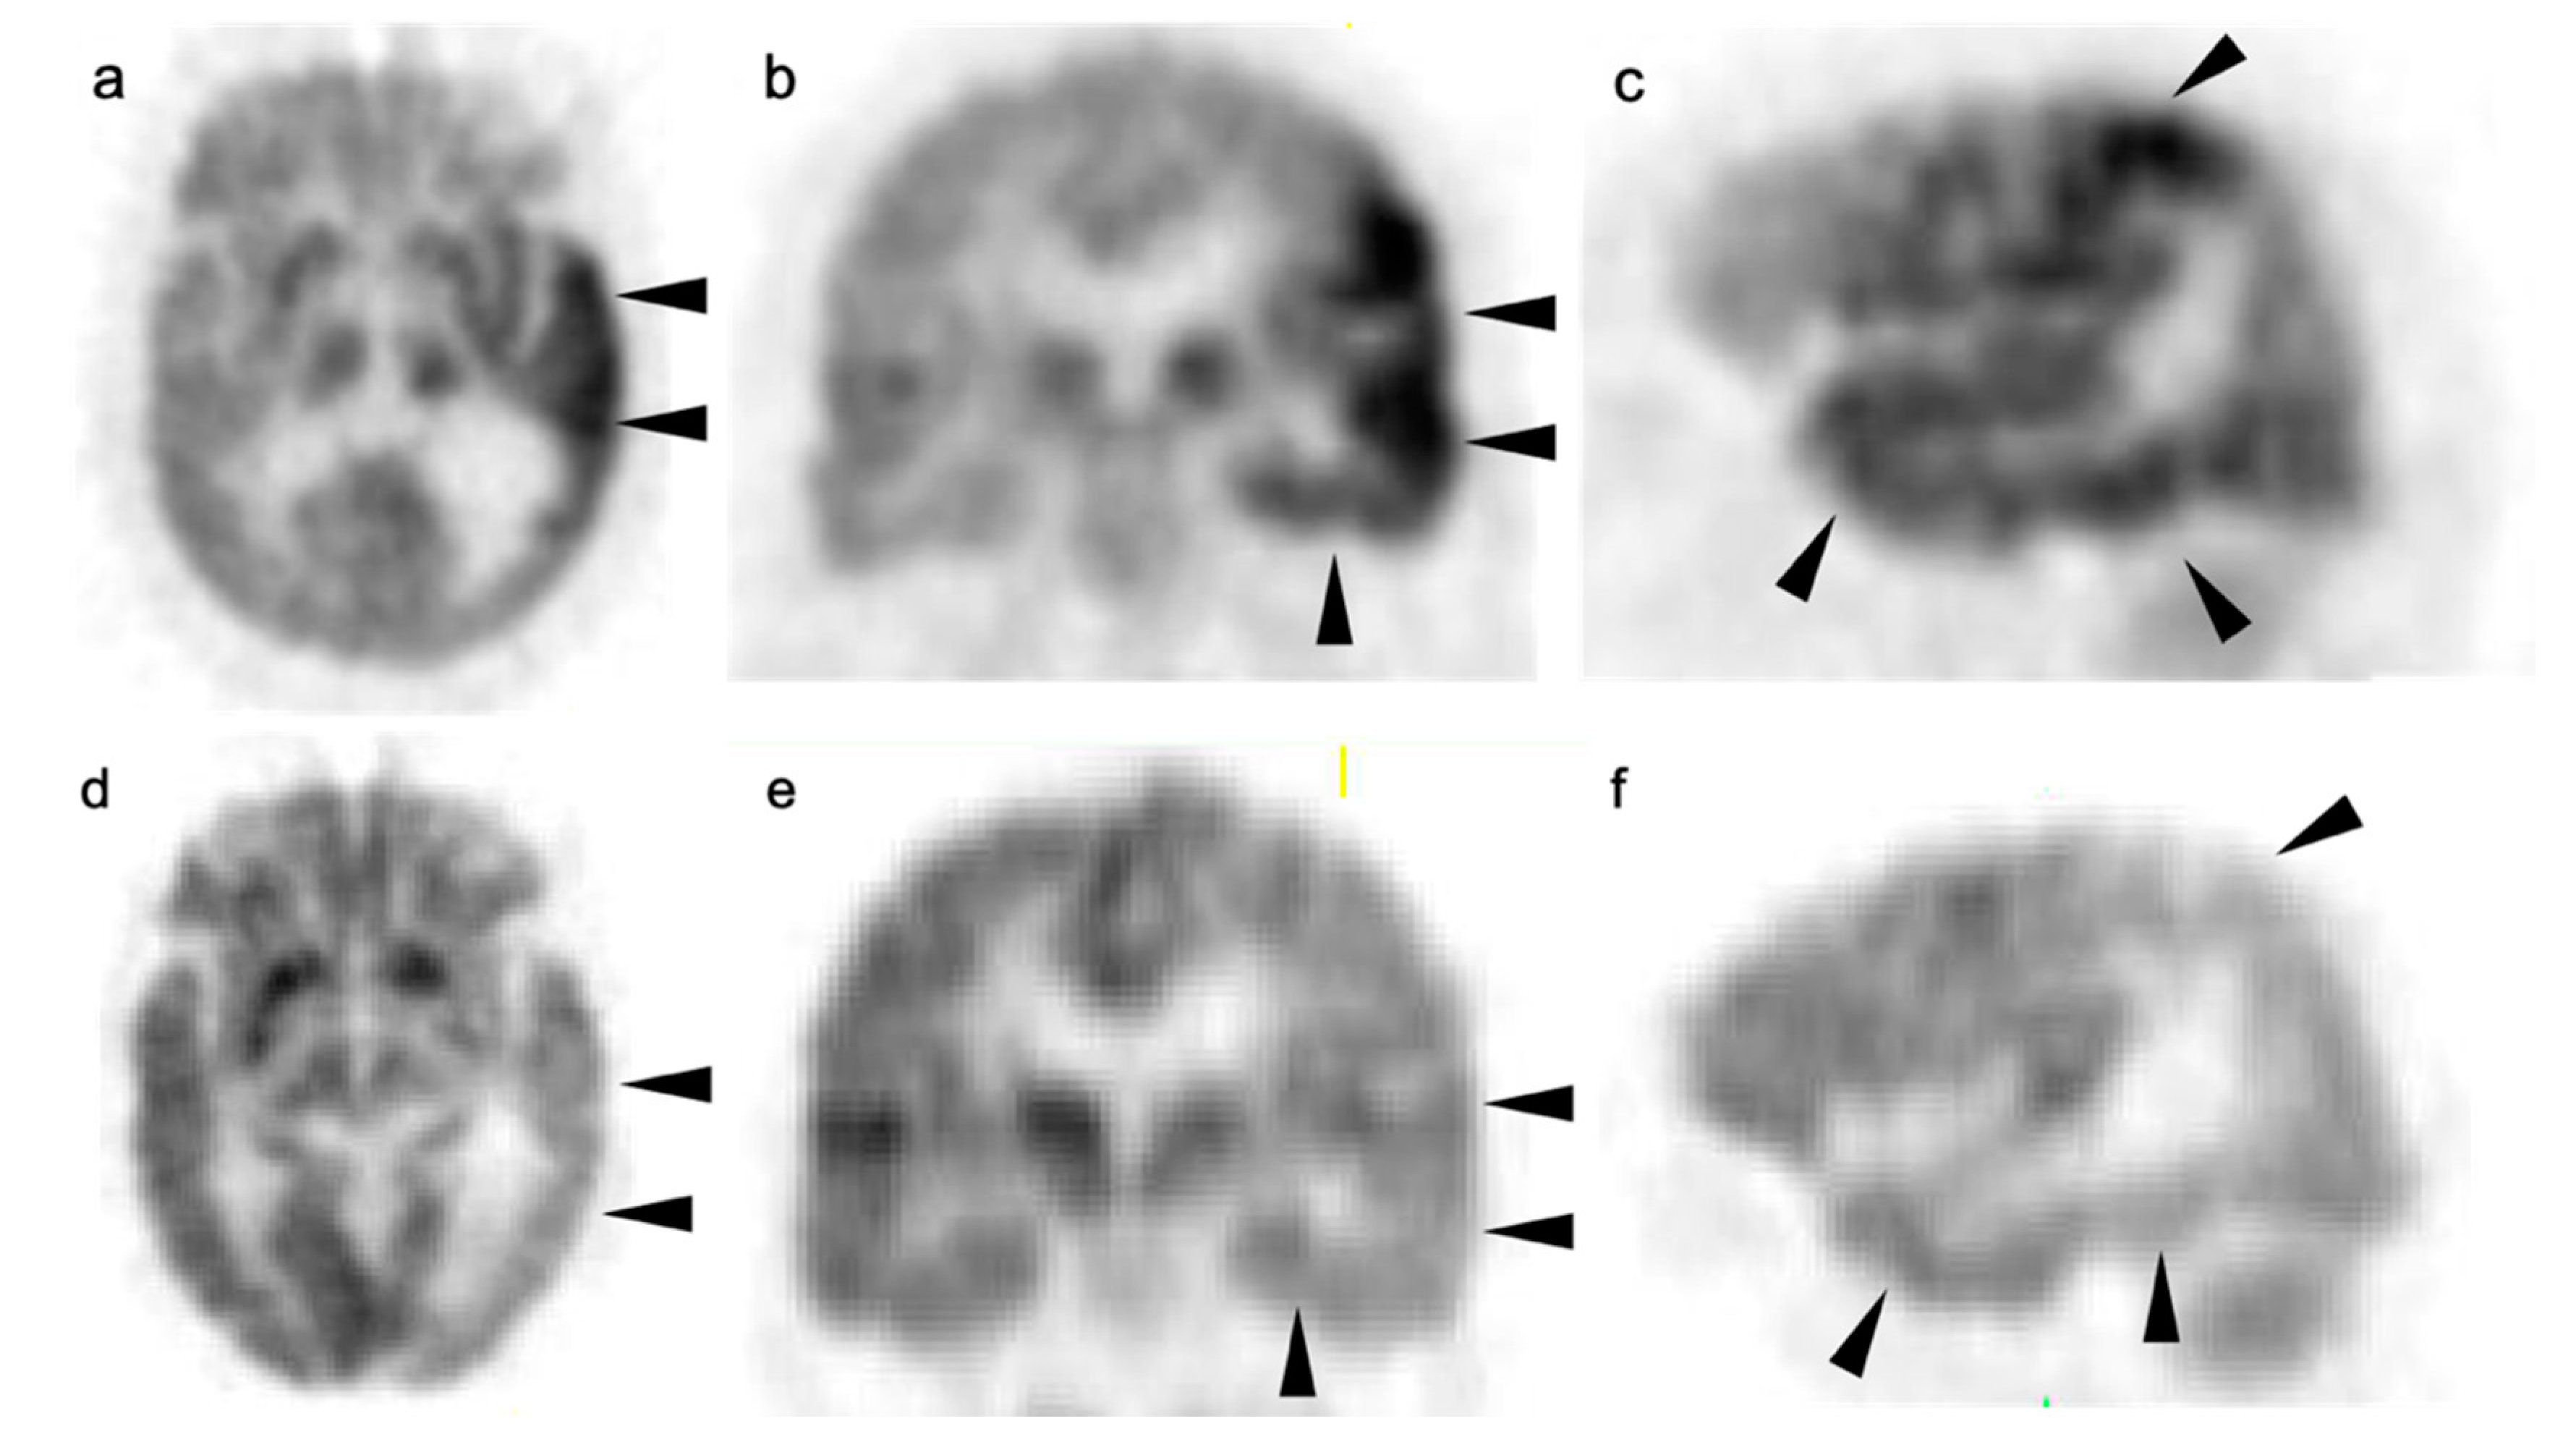

3.7. Meningioma

4. Conclusions